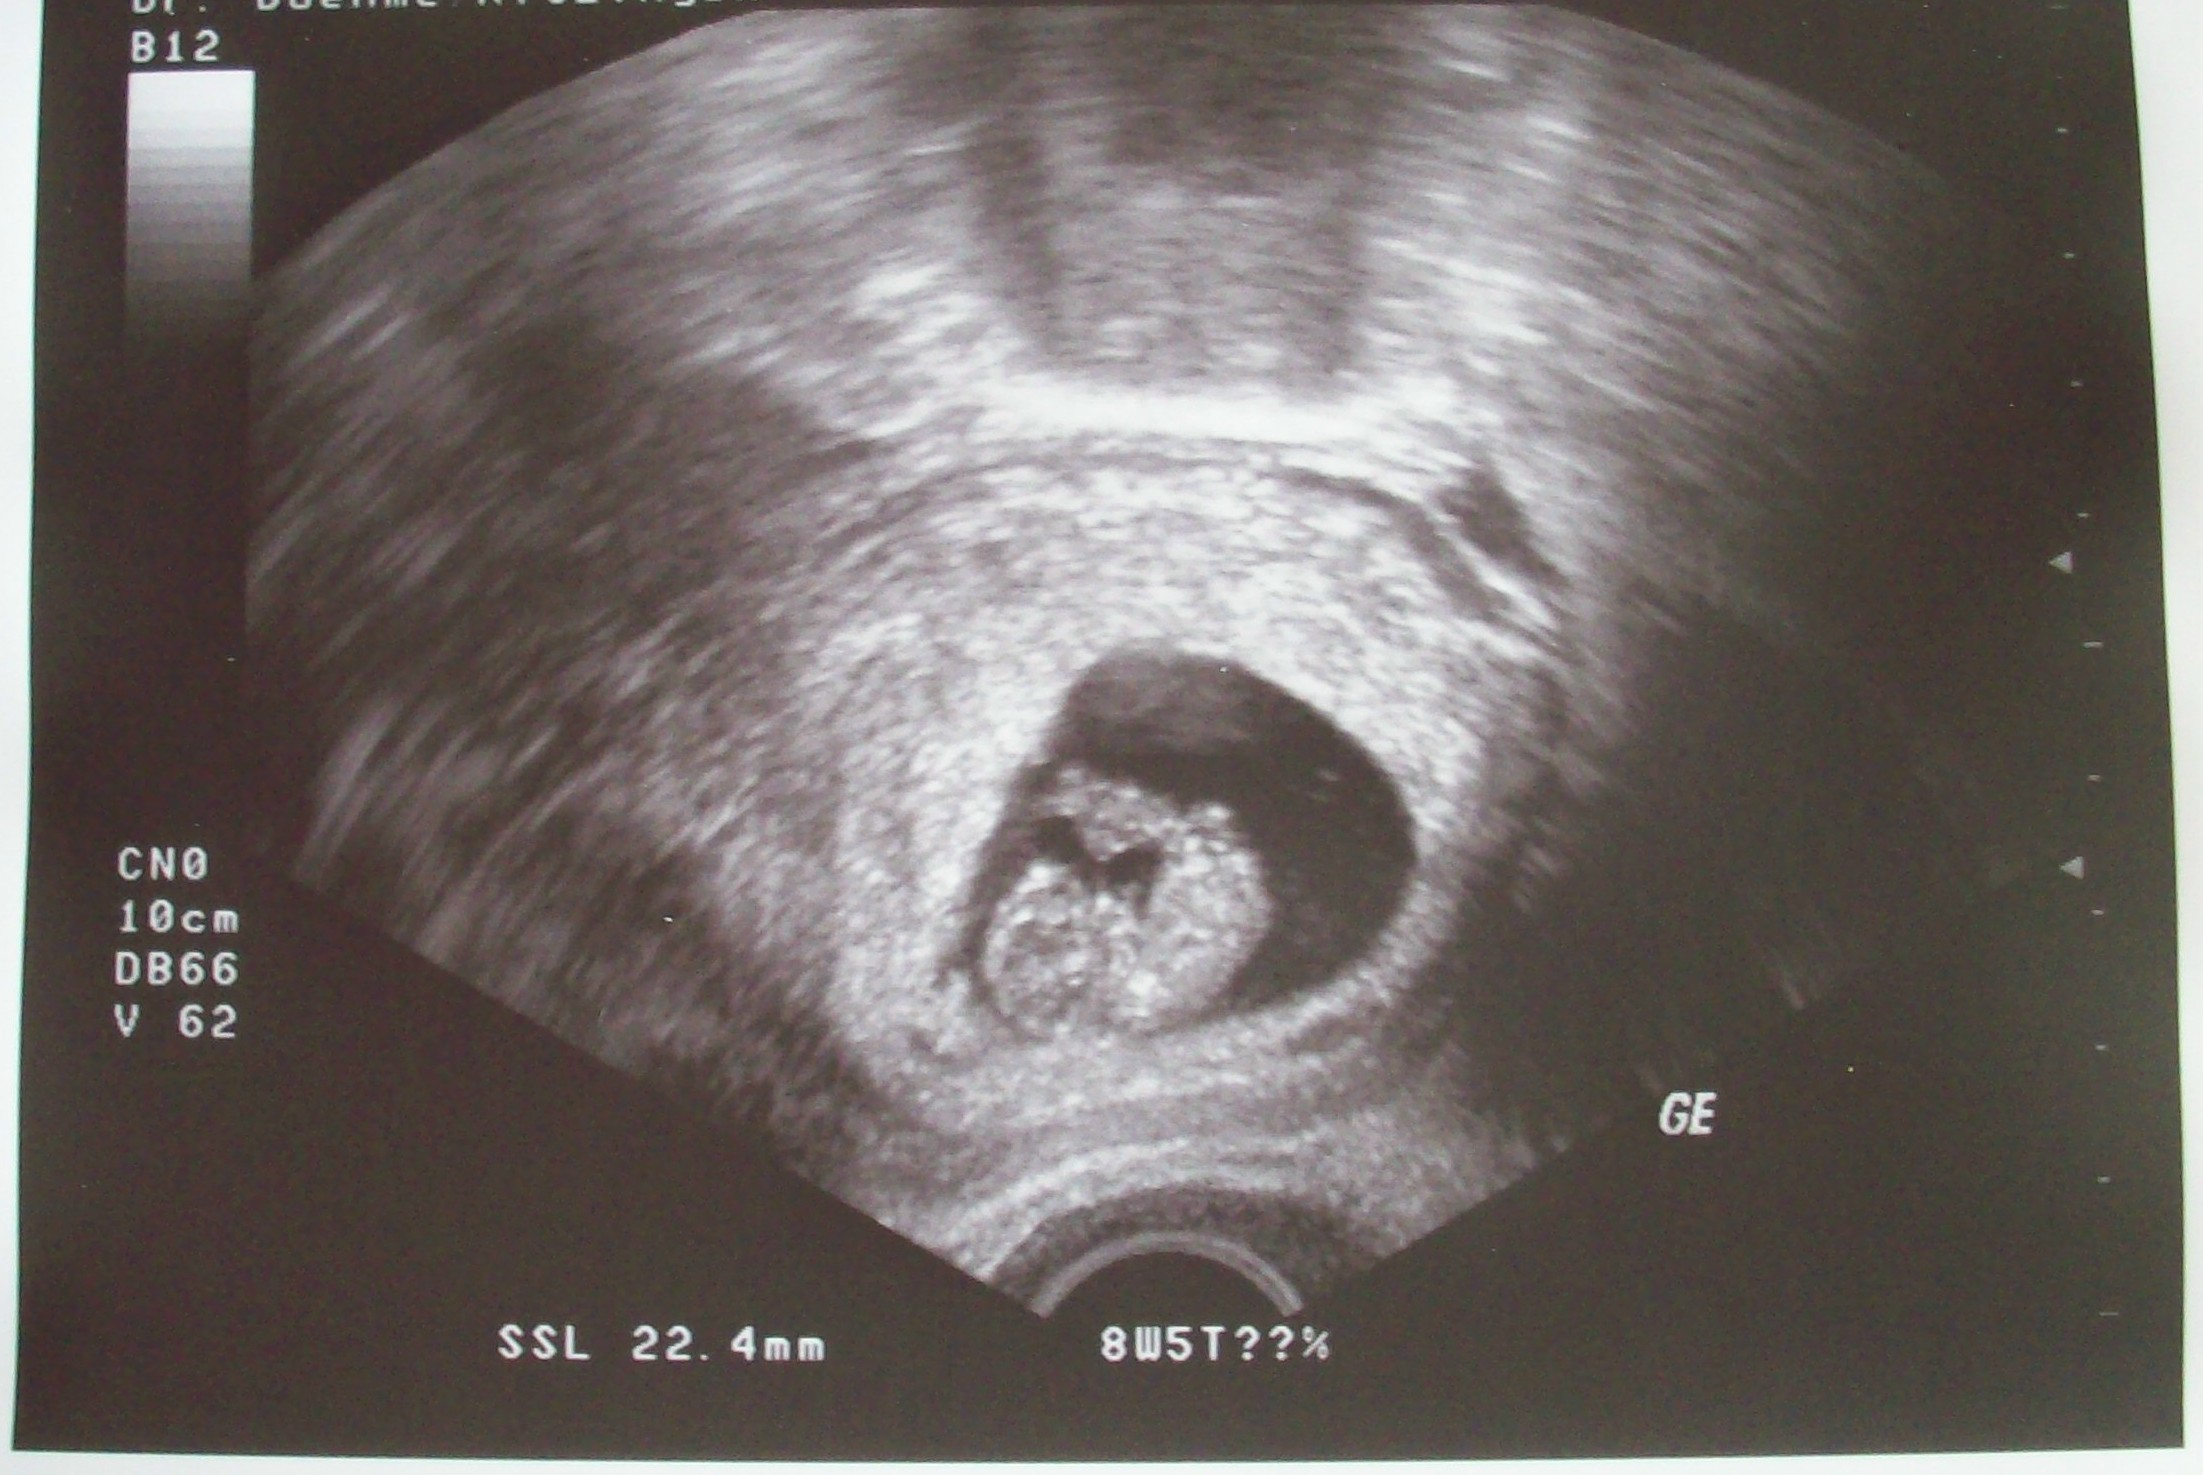

So, und hier mal das Krümelchen, kann es gar nicht glauben, das es in mir ist, kommt mir immer noch wie ein Traum vor.

Baby 3. US.jpg

Och Bikerbabe wie süß. Da muß man ja gleich wieder Bild Kann man ja schon richtig alles erkennen. :knuddel:

Das Bild sieht ja wirklich klasse aus. Man kann ja schon alles erkennen. Ja, sei ruhig Stolz auf dein kleines Würmchen. Es ist wie ein Wunder, dass in dir so etwas schönes wächst.